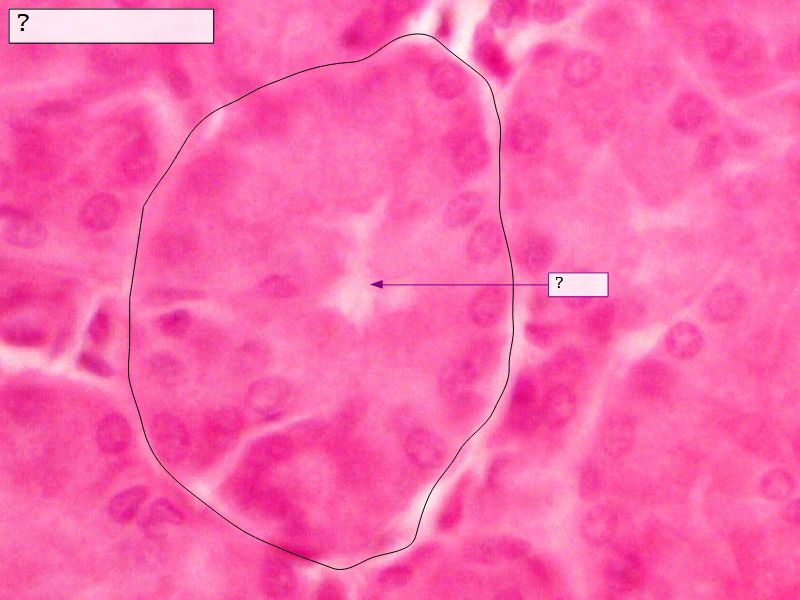

Fill in all the missing labels, and assess as you move through the slides. Answers on the down slide. It is important to do this using pen and paper, and not just glance through the images.